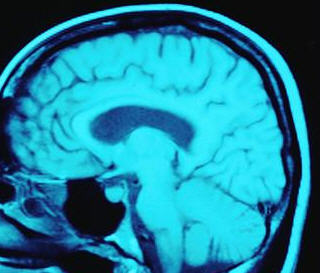

A neuropsychological evaluation utilizes standardized measures to assess an individual's cognitive ability and underlying brain function.